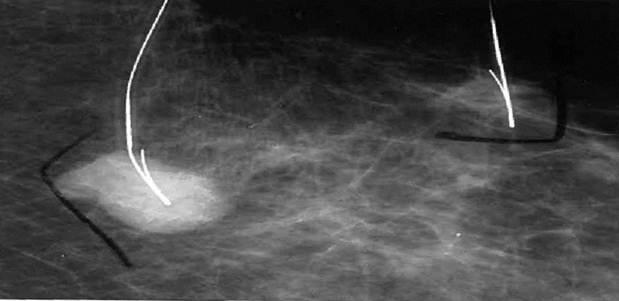

A 78 year old female presented to her primary care physician with a palpable lesion noted in her left breast, questionable axillary nodes and a second lesion in her right breast. The patient had no prior history of any medical or surgical illnesses and was not on any medication. A mammogram taken of both breasts revealed approximating lesions in the left breast (Fig. 1) and a single lesion in the right breast.

Figure 1

Demonstrates localization of two lesions of the left breast for biopsy.

In Figure 1, we are able to discern two discrete lesions of the left breast the nature of which were defined by core biopsy. The initial core biopsies of all three lesions were performed in the mammography department of North Shore Univ Hospital. The right breast proved to have a solitary lesion demonstrating predominantly lymphocytic pathology consistent with a B cell lymphoma. In the left breast 2 separate pathologic processes were defined, one an infiltrating ductal carcinoma (Fig. 2a, 2b) and in close proximity, a second lesion, the B-cell lymphoma (Fig 3a, 3b). No further surgery was performed on the right breast. The left breast underwent partial mastectomy. Nodes that were sampled from the left axilla were all negative.